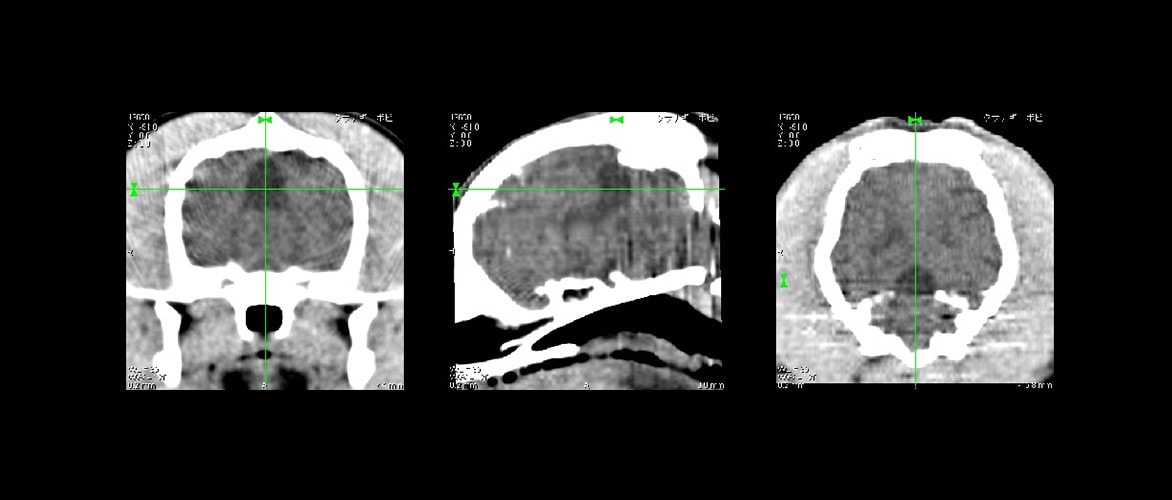

木馬様歩行を呈し来院。小脳疾患が疑われたためCT撮影を実施しました。小脳背側に認められる脳室のような低CT値のマスはクモ膜下嚢胞で、それによる物理的な小脳圧迫と診断されました。現在は脳圧を下げる治療を継続し症状は消失しました。

1週間ほど右斜頚が続きその後起立不能になり来院。左顔面神経麻痺が認められ大脳疾患が疑われCT撮影を実施しました。頭頂部やや左側に高いCT値のマスが認められます。これは血腫でした。ステロイドの内服にて除々に症状も消失し現在は経過良好です。